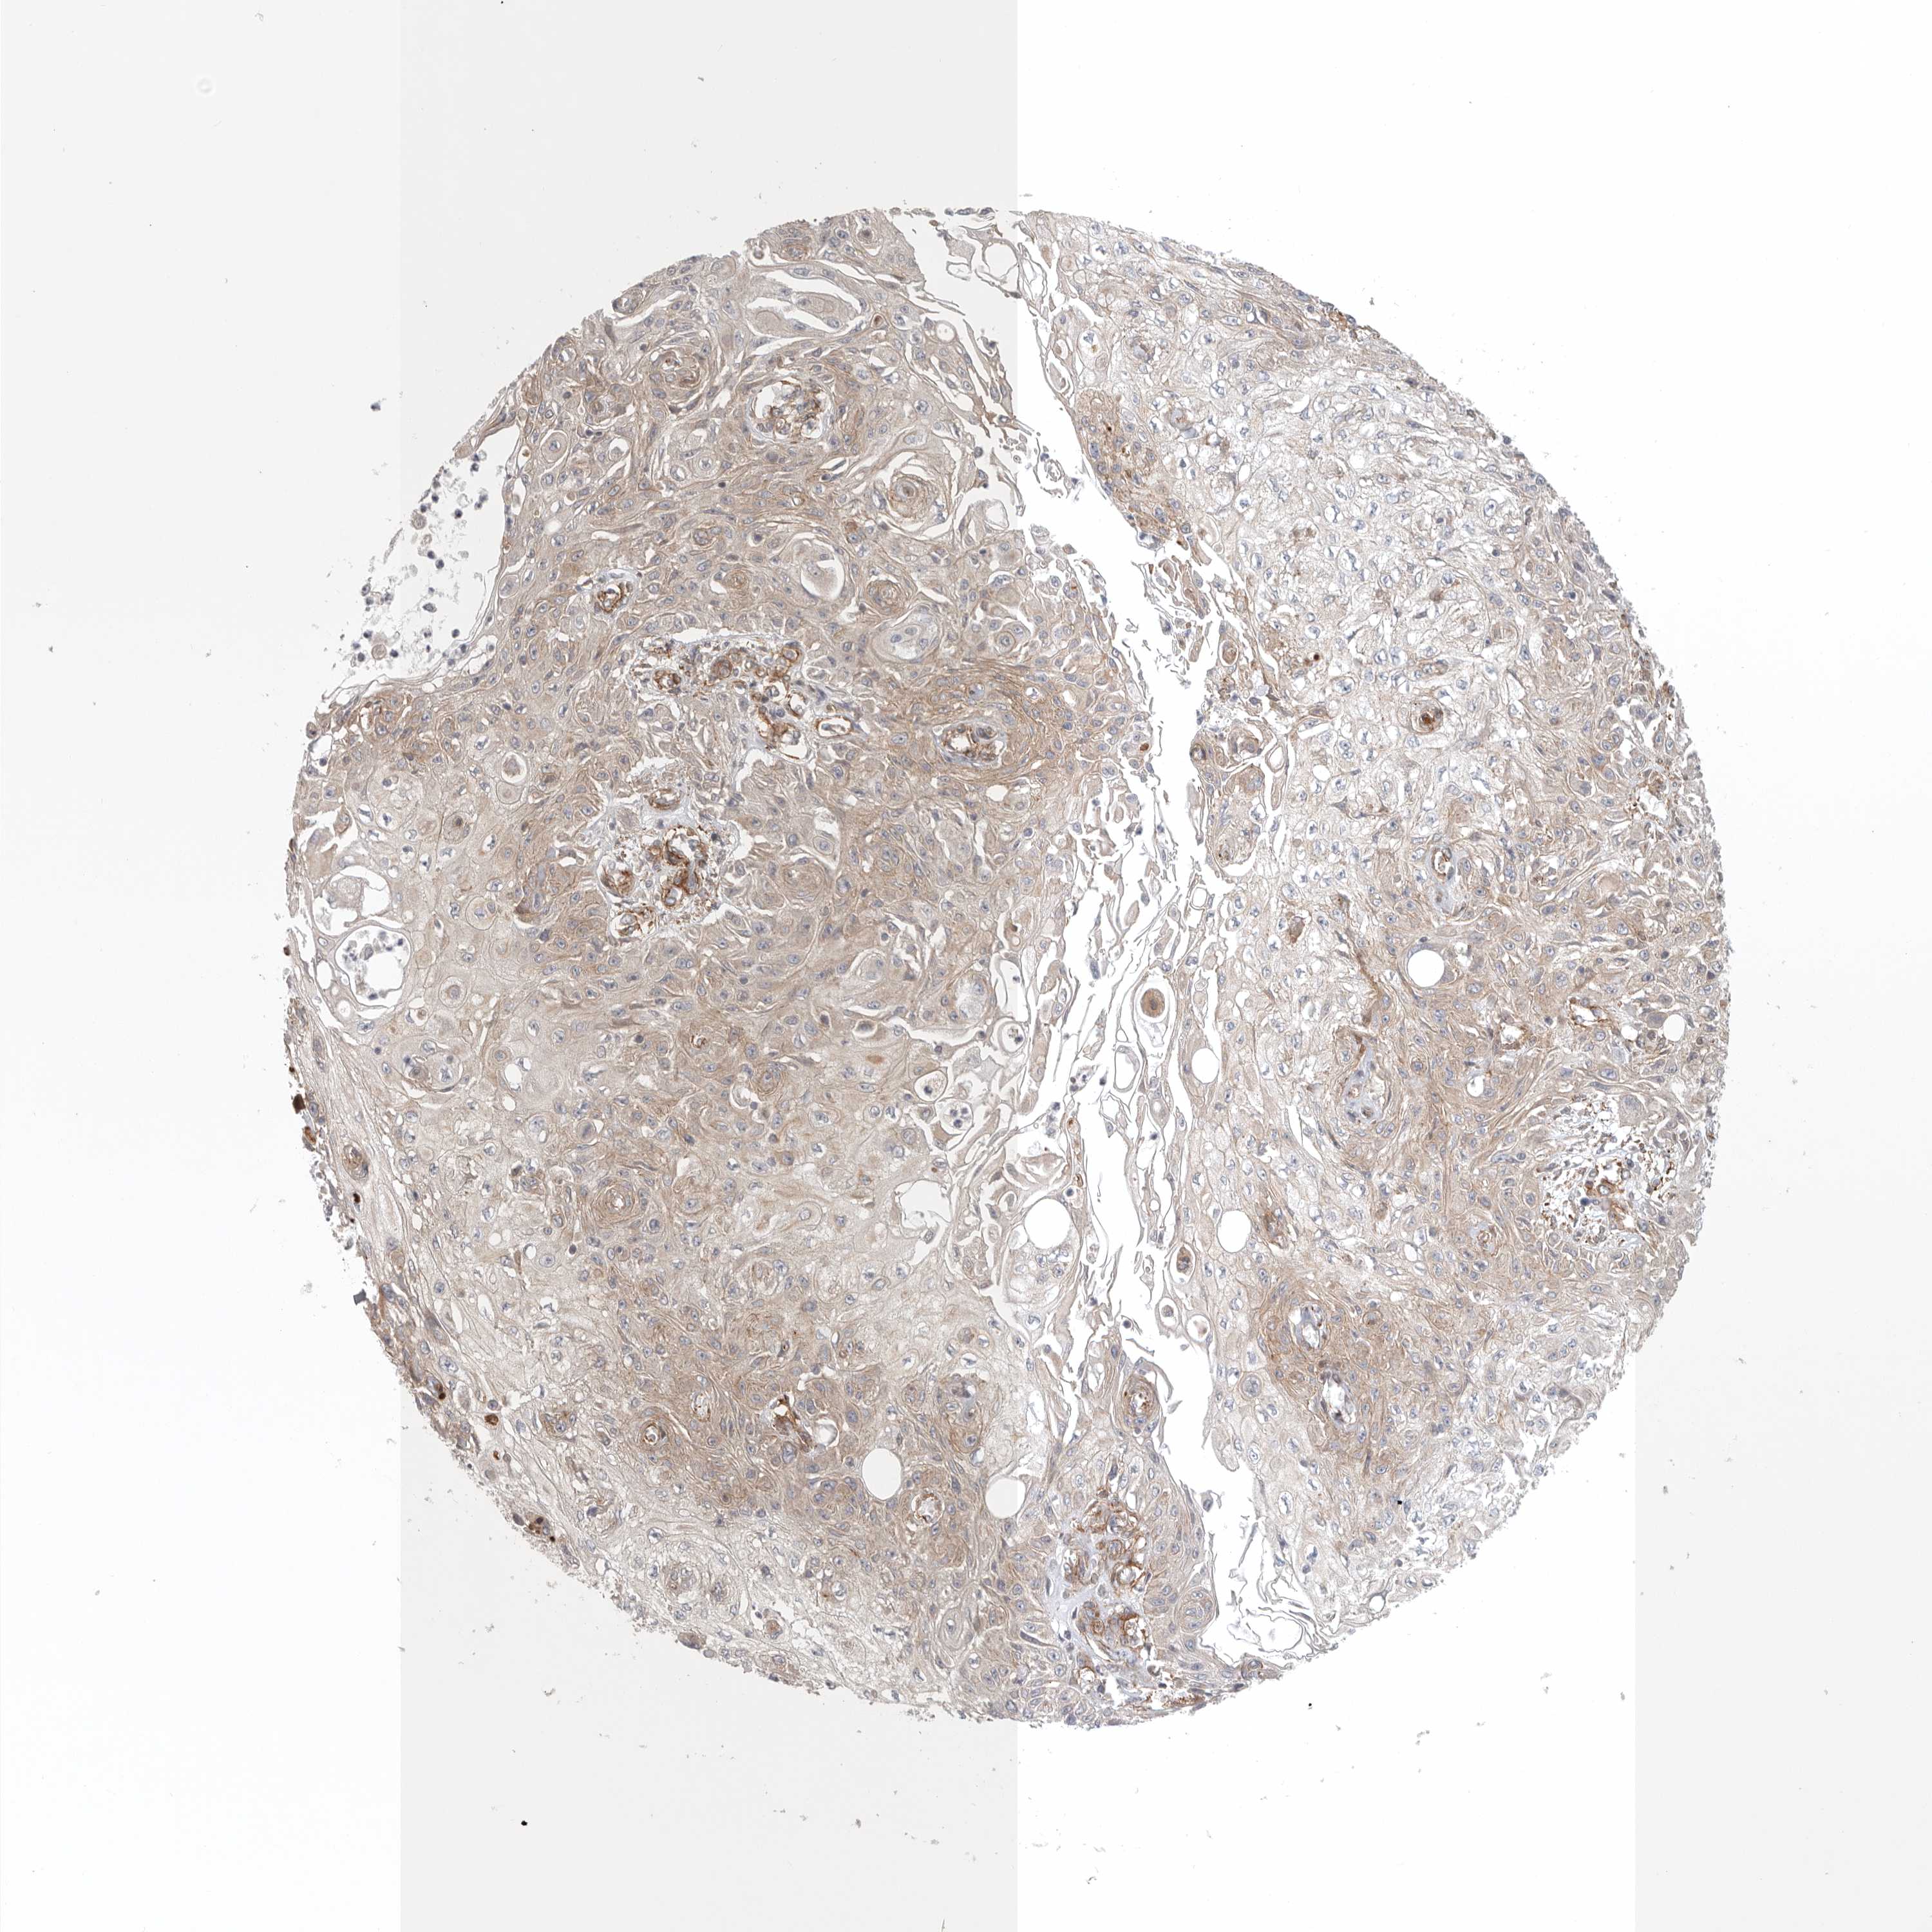

CANCER SKIN CANCER Show tissue menu

Basal cell and squamous cell cancer

SKIN CANCER - Protein expressioni

A mouse-over function shows sample information and annotation data. Click on an image to view it in a full screen mode. Samples can be filtered based on level of antibody staining by selecting one or several of the following categories: high, medium, low and not detected. The assay and annotation is described here.

Each image is clickable and will lead to virtual microscopy that enables deeper exploration of all samples and also displays staining intensity scores, fraction scores and subcellular localization as well as patient and tissue information for each sample.

Antibody HPA023584

Antibody HPA024814

Basal cell carcinoma

Squamous cell carcinoma, NOS

Squamous cell carcinoma, metastatic, NOS